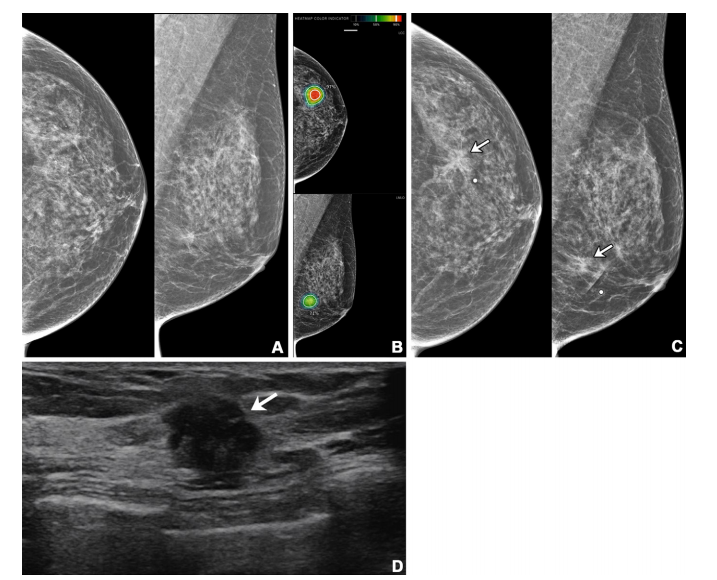

Figure 4: Imaging in a 56-year-old woman with heterogeneously dense breasts (Breast Imaging Reporting and Data System category c). (A) Left craniocaudal (left) and mediolateral oblique (right) digital mammograms show no abnormality. (B) Left craniocaudal (LCC, top) and left mediolateral oblique (LMLO, bottom) mammograms with retrospectively applied artificial intelligence (AI) (Lunit INSIGHT MMG, version 1.1.7.1; Lunit) show the lesion was given abnormality scores of 97% and 71%, respectively. The color bar indicates pixel-level abnormality scores corresponding to heatmap contour lines. Breast US performed the same day was considered negative (not shown). (C) Left craniocaudal (left) and mediolateral oblique (right) digital mammograms acquired 9 months later show an irregular mass (arrows) in the left breast, which correlates with the heatmap areas scored as 97% and 71% by AI in the earlier screening mammogram (B). The radiopaque round marker denotes the site of the palpable abnormality indicated by the patient. (D) Transverse US image shows an irregular mass (arrow) in the left breast. The patient was treated with breast-conserving surgery, and the mass was proven to be invasive lobular carcinoma (pT2N1, 2.5 cm in size, estrogen receptor and progesterone receptor negative, human epidermal growth factor receptor 2 positive, histologic grade 3).

图4: 影像显示一名56岁乳腺结构异质性致密的女性(乳腺影像报告与数据系统分类c)。(A) 左侧头尾位(左)和中斜位(右)数字乳腺X线照片显示未见异常。(B) 左侧头尾位 (LCC, 上) 和左侧中斜位 (LMLO, 下) 乳腺X线照片在回顾时应用人工智能(AI)(Lunit INSIGHT MMG,版本1.1.7.1;Lunit)分析后,显示病灶分别被赋予97%和71%的异常评分。颜色条表示与热图轮廓线对应的像素级异常评分。同一天进行的乳腺超声检查被认为是阴性(未显示)。(C) 9个月后获取的左侧头尾位(左)和中斜位(右)数字乳腺X线照片显示左乳房有一个不规则肿块(箭头),与早期筛查乳腺X线照片 (B) 中AI赋予97%和71%评分的热图区域相对应。不透明圆形标记表示患者指出的可触及异常位置。(D) 横断面超声图像显示左乳房内有一个不规则肿块(箭头)。患者接受了乳腺保留手术,肿块被证实为浸润性小叶癌(pT2N1,大小2.5厘米,雌激素受体和孕激素受体阴性,HER2阳性,组织学等级为3)。